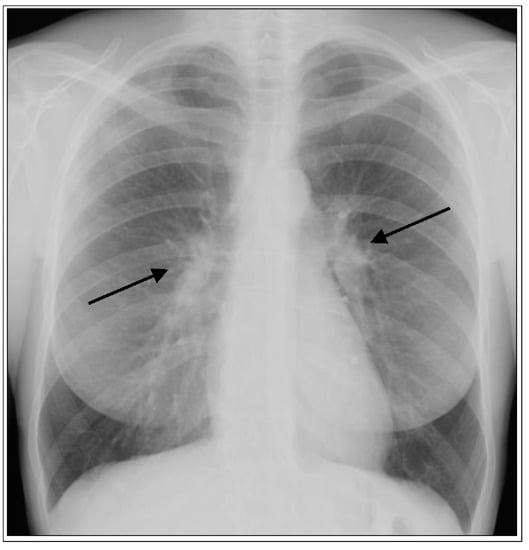

1.1. Lung

- Nunes, H.; Uzunhan, Y.; Gille, T.; Lamberto, C.; Valeyre, M.; Brillet, P.-Y. Imaging of sarcoidosis of the airways and lung parenchyma and correlation with lung function. Eur. Respir. J. 2012, 40, 750–765. [Google Scholar] [CrossRef] [PubMed]